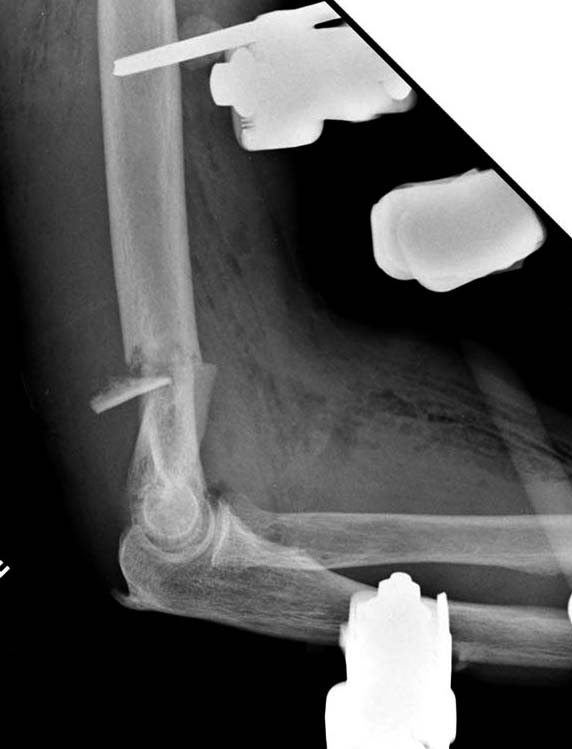

Примеры: первому более 15 лет фиксирован шурупом и tension band

technique, а второй перелом открытый больной 80 лет, после наружного

фиксатора в первом этапе и окончательная фиксация вторично. Третьий раз

внесуставная остеотомия...

Имя     : 3-2 Humerus prox distal exfix.jpg

Тип     : image/jpeg

Размер  : 43483 байтов

Описание: отсутствует

Url     : http://weborto.net:8080/pipermail/ortho/attachments/20130604/c45a379f/attachment-0028.jpg